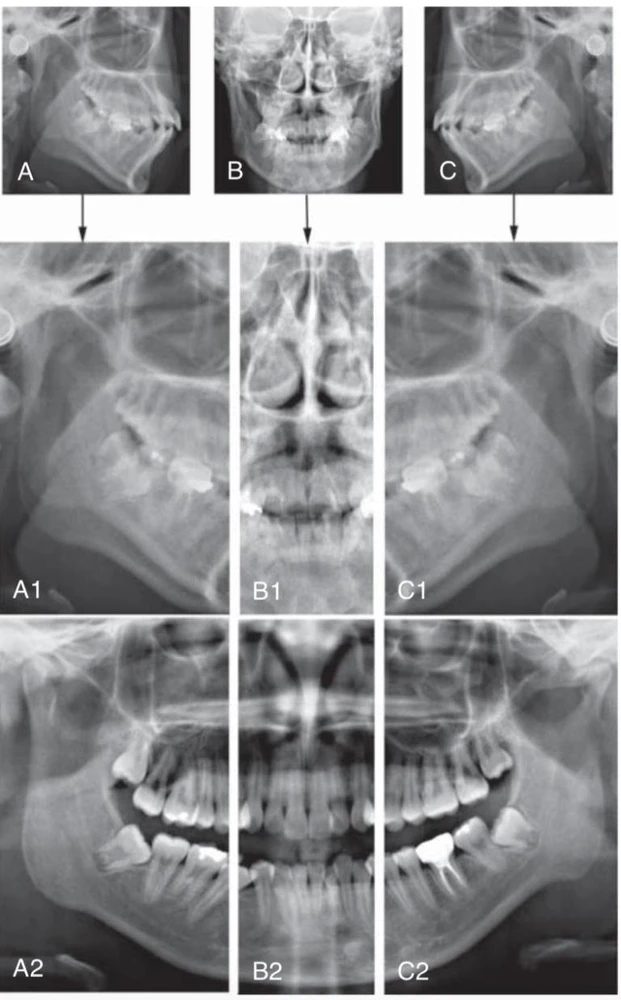

Nhà lâm sàng nên quan sát hình ảnh như thể nhìn vào bệnh nhân, với những cấu trúc bên phải của bệnh nhân sẽ nằm phía bên trái của người xem ảnh. Vì vậy hình ảnh được hiển thị cùng chiều như với hình ảnh trên phim quanh chóp và phim cánh cắn, giúp việc phân tích phim dễ dàng hơn. Điều cực kỳ quan trọng là nhận ra các mặt phẳng của bệnh nhân thể hiện trên những phần khác nhau của phim toàn cảnh. Hình ảnh trên phim toàn cảnh thật ra gồm ba hình ảnh: hình ảnh bên phải và bên trái phía sau răng nanh và một hình ảnh theo chiều trước sau từ phía trước cho đến vị trí răng nanh. Phần phía trước cũng bị biến dạng nhiều nhất và bị chồng với những cấu trúc từ đốt sống cổ. Vì vậy, phương pháp tiếp cận bằng cách hình dung phim toàn cảnh gồm hai phần hình ảnh chụp phía bên quanh một phần ảnh chụp theo chiều trước sau ở giữa, một loại hình chiếu Mercator của mặt giữa và mặt dưới. Phương pháp hình dung này cho phim toàn cảnh được mình hoạ ở hình bên dưới.